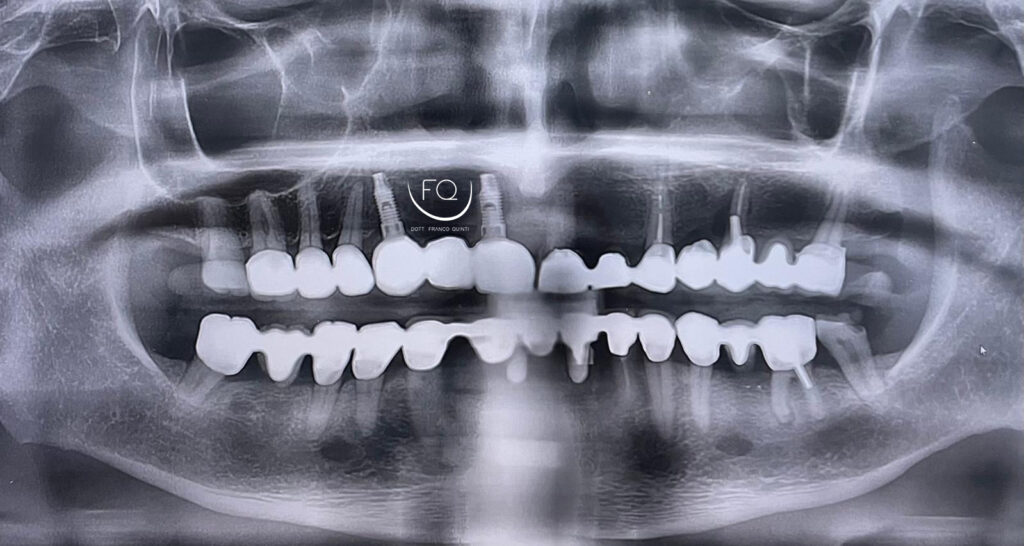

Questa settimana vi presento un caso di chirurgia computer guidata monolaterale, eseguito con l’utilizzo di una dima scomponibile ad appoggio dentale.

Durante l’intervento sono stati inseriti tre impianti PRAMA 3.8 × 11.5 di Sweden & Martina, successivamente sottoposti a carico immediato.